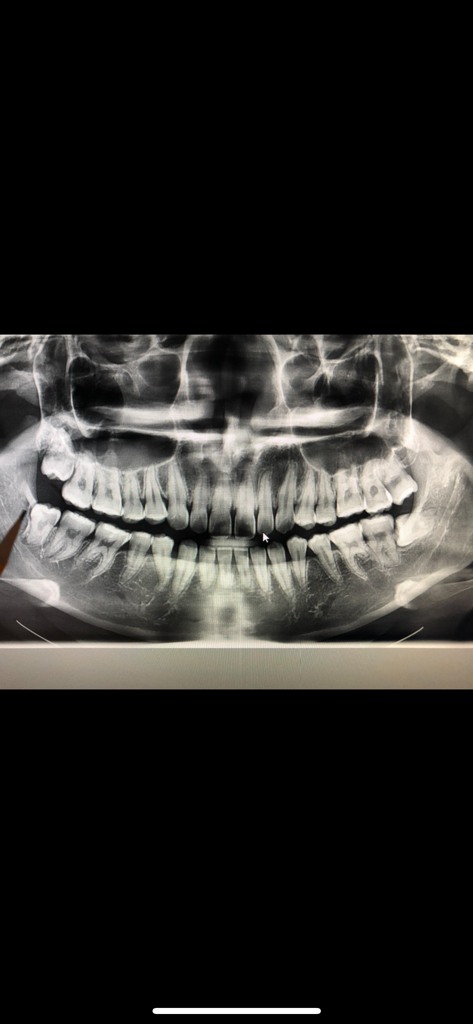

1. 위, 아래 사랑니 둘다 보통정도의 난이도 입니다.

2. 아래 사랑니의 경우 뼈에 걸려 잘 안나오면 잇몸 째고 뼈를 일부 갈아낸 뒤 발치하는 서지컬 발치를 할 수도 있긴 합니다. 가능성의 부분입니다.

3. 신경관과 그렇게 근접하진 않습니다.

저정도면 크게 난이도가 잇는 케이스는 아닙니다. 신경손상 가능성은 낮아 보이니 걱정하지 않으셔도 될것같습니다.

상악에 있는 사랑니는 나오는데 크게 힘이 들거나 하진 않습니다. 하지만 깊게 들어가 있기 때문에 도구가 접근하기 힘들 수도 있습니다. 발치를 하는 데 상대적으로 다른 치아보다는 난이도가 높을 수 있지만 엄청 어려운 난이도는 아닐 것으로 생각됩니다.

난이도는 꽤 있어 보이고 신경과의 거리도 가까운 편입니다만 경험많으신 원장님은 금방 뽑을 겁니다.